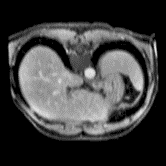

In clinical practice, well-aligned multi-modal images, such as Magnetic Resonance (MR) and Computed Tomography (CT), together can provide complementary information for image-guided therapies. Multi-modal image registration is essential for the accurate alignment of these multi-modal images. However, it remains a very challenging task due to complicated and unknown spatial correspondence between different modalities. In this paper, we propose a novel translation-based unsupervised deformable image registration approach to convert the multi-modal registration problem to a mono-modal one. Specifically, our approach incorporates a discriminator-free translation network to facilitate the training of the registration network and a patchwise contrastive loss to encourage the translation network to preserve object shapes. Furthermore, we propose to replace an adversarial loss, that is widely used in previous multi-modal image registration methods, with a pixel loss in order to integrate the output of translation into the target modality. This leads to an unsupervised method requiring no ground-truth deformation or pairs of aligned images for training. We evaluate four variants of our approach on the public Learn2Reg 2021 datasets \cite{hering2021learn2reg}. The experimental results demonstrate that the proposed architecture achieves state-of-the-art performance. Our code is available at https://github.com/heyblackC/DFMIR.